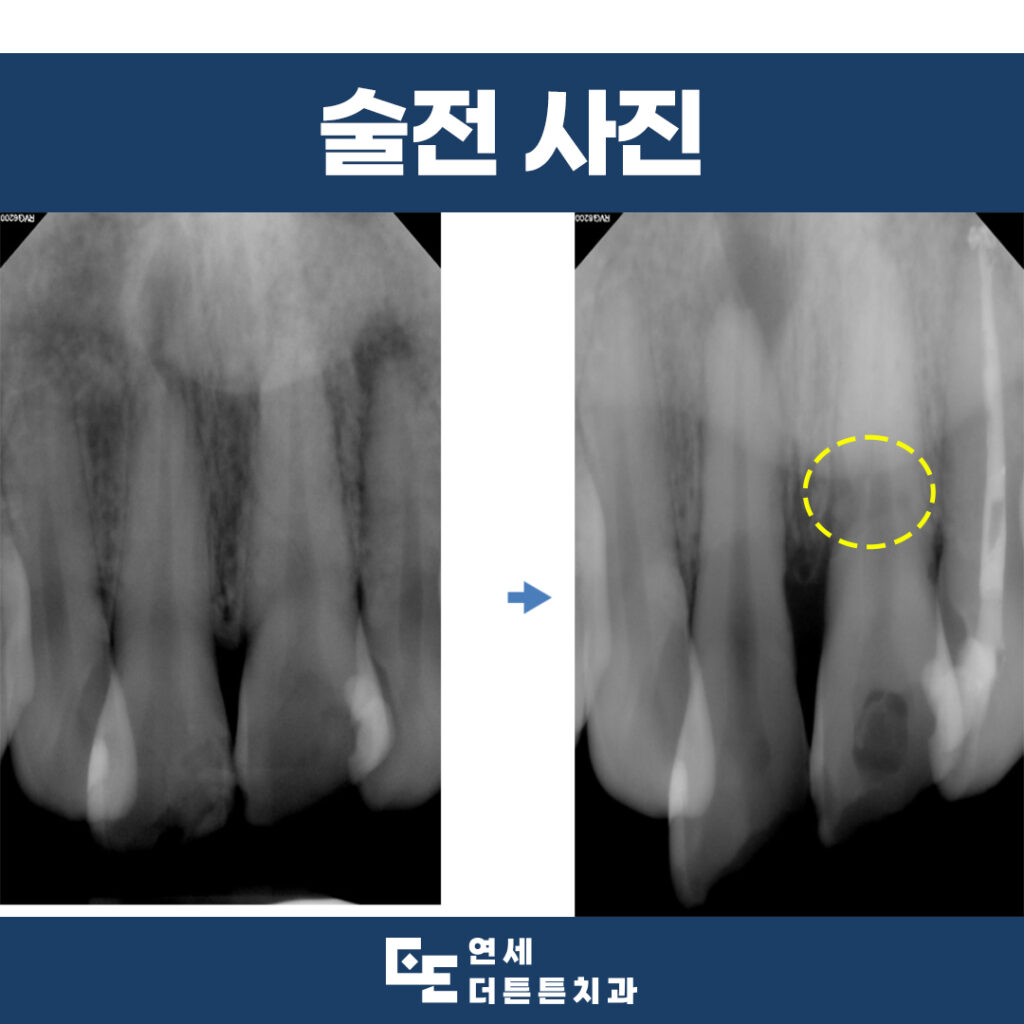

내원 당시 구내 사진과

x-ray 사진을 통해 진단해 본 결과,

옆여 있는 치아들도 충격을 받아

신경치료가 필요한 부위는 진행을

하기로 하였습니다.

전반적으로 6개의 앞니 모두

예후가 좋지 않음을 고려하여

장기적으로 계획을 수립하였습니다.